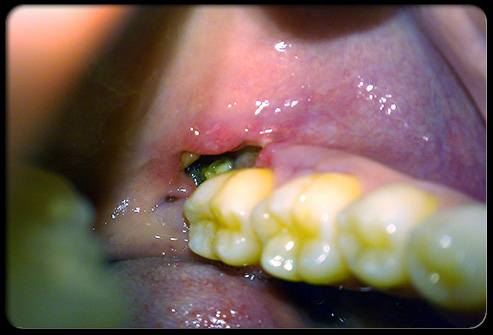

حفره خشک

پس از کشیدن دندان، ممکن است لخته خونی که در حالت طبیعی حفره خالی را پر میکند تشکیل نشود که به این وضعیت حفره خشک (dry socket) گفته میشود. حفره خشک باعث میشود عصبهای زیر حفره رخنمون پیدا کنند که حاصل آن بسیار دردناک خواهد بود. دندانپزشک با تمیز کردن زخم و پانسمان ویژه ای در حفره دندان، این وضعیت را درمان میکند. داروهای ضد التهاب بدون نسخه مانند ایبوپروفن نیز ممکن است برای درمان درد و کاهش تورم استفاده شوند.